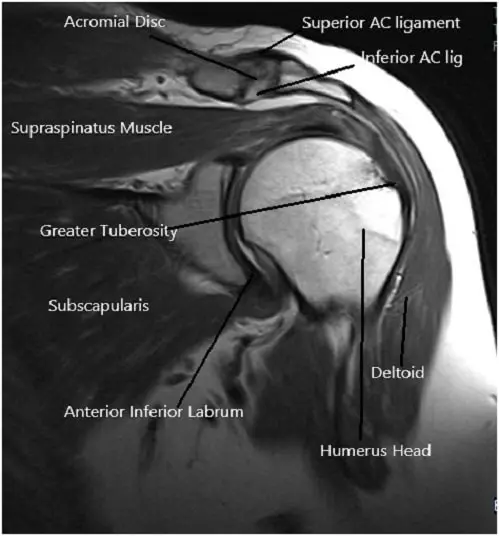

La resonancia magnética del hombro izquierdo sugirió tendinosis del tendón supraespinoso con una ruptura parcial de la superficie articular de las fibras anteriores y medias del tendón. Tendinosis del tendón infraespinoso. Líquido bursal subacromial/subdeltoideo que refleja bursitis. Degeneración y desgarro del labrum anterosuperior.

Imagen por resonancia magnética del hombro en secciones axial y coronal